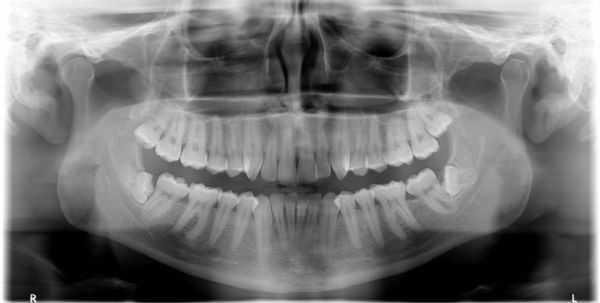

(Слева) На фотографии виден вывих центрального резца верхней челюсти слева в сторону губы (вариант бокового вывиха).

(Справа) На периапикальной рентгенограмме у этого же пациента не определяются изменения в этой плоскости, поскольку зуб смещен в сторону губы. На КЛКТ (исследование в этом случае не было доступно) может обнаруживаться расширение пространства периодонтальной связки (НДС) со стороны губы. Была выполнена ручная репозиция зуба и шинирование. (Слева) На периапикальной рентгенограмме у этого же пациента через десять лет после травмы определяется, что вершина корня зуба закрыта; вмешательство на каналах не требуется. Пульпа пораженного зуба обызвествлена, скорее всего, в от вет на травму.

(Справа) На периапикальной рентгенограмме определяется вколачивание и перелом резцового края центрального и бокового резцов слева. Обратите внимание на отсутствие пространства ПДС в области вершины корня центрального резца. (Слева) На периапикальной рентгенограмме состояние после репозиционирования и стабилизации вколоченных центрального и бокового резцов проволокой и композитной шиной. Обратите внимание на признаки рарефицирующего остеита рядом с вершиной корня бокового резца.

(Справа) На контрольной периапикальной рентгенограмме у этого же пациента определяется внутренняя и наружная резорбция зубов, т.к. лечение корневых каналов было начато, но не завершено.